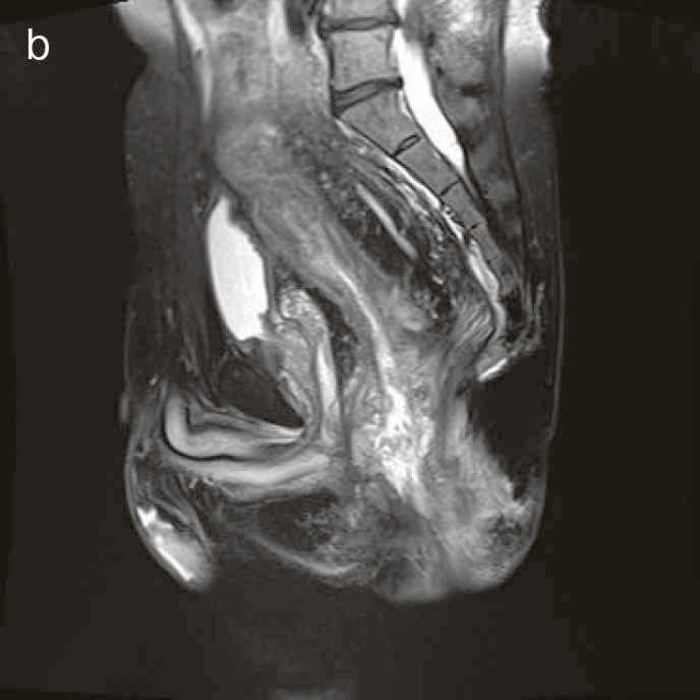

図38 骨盤部MRI

術前の骨盤部MRIでは右側の痔瘻瘻管と,左側の瘻管,周囲のリンパ節腫大を認めた。

明らかな癌を示す所見は不明であった。